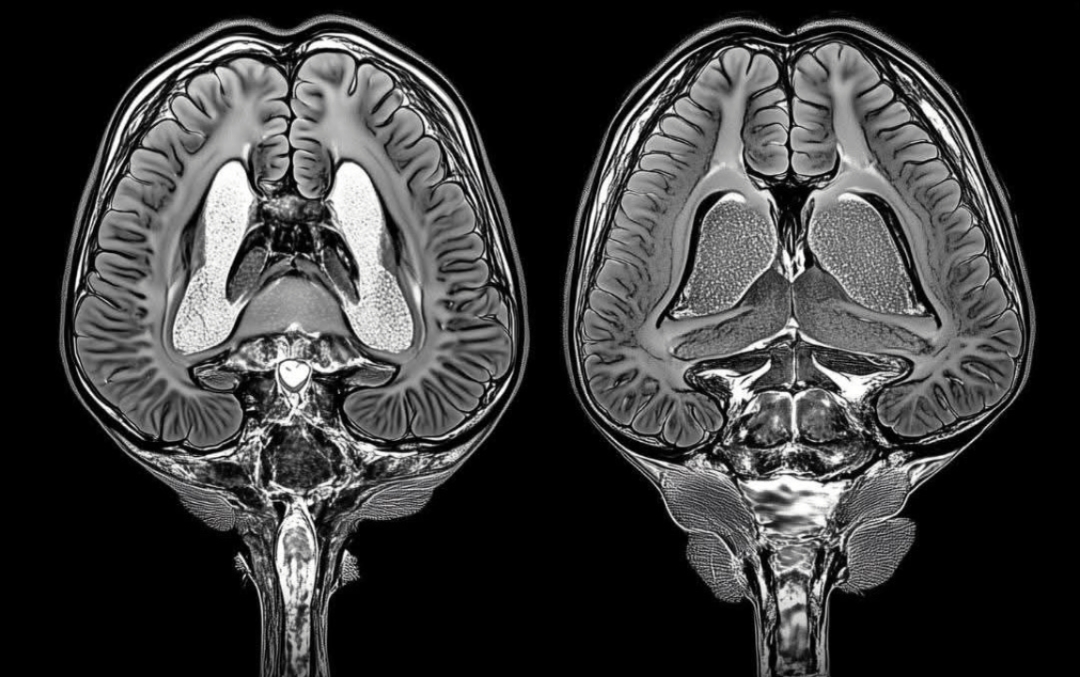

এবার আসি মস্তিষ্কের প্রসঙ্গে। আমাদের মস্তিষ্ক কোটি কোটি স্নায়ুকোষের সমন্বয়ে গঠিত, আর এই স্নায়ুকোষগুলোর মধ্যে সংযোগ তৈরি হয় যেগুলোকে বলে সিন্যাপস। এই সিন্যাপসের মাধ্যমেই আমরা নতুন কিছু শিখি, মনে রাখি কিংবা চিন্তা করি। কিন্তু সব সিন্যাপস সমানভাবে দরকারি নয়। অনেক সময় কিছু সংযোগ দুর্বল হয় কিংবা একেবারেই অপ্রয়োজনীয় হয়ে পড়ে। যেমন ধরুন, আপনার টেবিলে যদি অগণিত কাগজপত্র আর বইপত্র জমে থাকে, তবে দরকারি জিনিস খুঁজে পাওয়া কঠিন হয়ে যায়। তাই অপ্রয়োজনীয় জিনিস সরিয়ে ফেলা জরুরি। ঠিক একইভাবে, মস্তিষ্কও তার অপ্রয়োজনীয় সিন্যাপসগুলো সরিয়ে ফেলে নতুন তথ্য শেখা এবং গুরুত্বপূর্ণ জিনিস মনে রাখার জায়গা তৈরি করে। এই কাজটি করে মস্তিষ্কের বিশেষ ফ্যাগোসাইট কোষ, যাদের বলা হয় মাইক্রোগ্লিয়া।

মাইক্রোগ্লিয়া একেবারেই দক্ষ পরিচ্ছন্নতাকর্মীর মতো কাজ করে। তারা দুর্বল বা অপ্রয়োজনীয় সিন্যাপস শনাক্ত করে এবং ধীরে ধীরে খেয়ে ফেলে। এই প্রক্রিয়াটিকে বলা হয় সিন্যাপটিক প্রুনিং। একে তুলনা করা যায় গাছের শুকনো ডাল ছেঁটে ফেলার সঙ্গে। শুকনো ডাল সরিয়ে ফেললে গাছ নতুন ডালপালা গজাতে পারে, ভালোভাবে বেড়ে উঠতে পারে। তেমনি মস্তিষ্কও পুরনো বা অনাবশ্যক সংযোগ বাদ দিয়ে নতুন সংযোগ গড়ে তোলে। এর ফলে শেখার ক্ষমতা বাড়ে, স্মৃতিশক্তি হয় আরও তীক্ষ্ণ, আর চিন্তাভাবনাও দ্রুতগতিতে হয়।

এই সিন্যাপটিক প্রুনিং আসলে আমাদের জীবনের বিভিন্ন পর্যায়ে ঘটে। শিশু বয়সে আমরা অসংখ্য জিনিস শিখি। তখন মস্তিষ্কে প্রচুর সিন্যাপস তৈরি হয়। কিন্তু সবগুলো সমানভাবে কাজে লাগে না। বড় হওয়ার সঙ্গে সঙ্গে মস্তিষ্ক অপ্রয়োজনীয় সংযোগ সরিয়ে দেয়, যাতে দরকারি জিনিসগুলো আরও শক্তভাবে মনে থাকে। কিশোর বয়সে এই প্রক্রিয়া সবচেয়ে বেশি ঘটে। এ সময় আমরা দ্রুত শেখার ক্ষমতা অর্জন করি, কিন্তু একই সঙ্গে মস্তিষ্কও অপ্রয়োজনীয় সংযোগ ছেঁটে ফেলার কাজে ব্যস্ত থাকে। ফলে দক্ষতা এবং মনোযোগ বাড়ে। এমনকি প্রাপ্তবয়স্ক বয়সেও মস্তিষ্ক সময় সময় প্রুনিংয়ের মাধ্যমে নিজেকে নতুন করে সাজায়।

তবে এও সত্যি, যদি ফ্যাগোসাইটোসিস এবং সিন্যাপটিক প্রুনিংয়ের প্রক্রিয়া নিয়ন্ত্রণের বাইরে চলে যায়, তাহলে তা মস্তিষ্কের জন্য ক্ষতিকর হতে পারে। গবেষণা বলছে, অ্যালঝাইমারস কিংবা পারকিনসন্সের মতো স্নায়বিক রোগের সঙ্গে এই প্রক্রিয়ার সম্পর্ক রয়েছে। যখন মস্তিষ্ক অতি মাত্রায় সিন্যাপস ছেঁটে ফেলে, তখন প্রয়োজনীয় সংযোগও হারিয়ে যেতে পারে। এর ফলে স্মৃতিভ্রংশ বা শেখার সমস্যা দেখা দিতে পারে। আবার যদি প্রক্রিয়াটি যথেষ্ট সক্রিয় না হয়, তবে অপ্রয়োজনীয় সংযোগ জমে থেকে বিভ্রান্তি তৈরি করতে পারে। তাই এই ভারসাম্য বজায় রাখা মস্তিষ্কের জন্য অপরিহার্য।